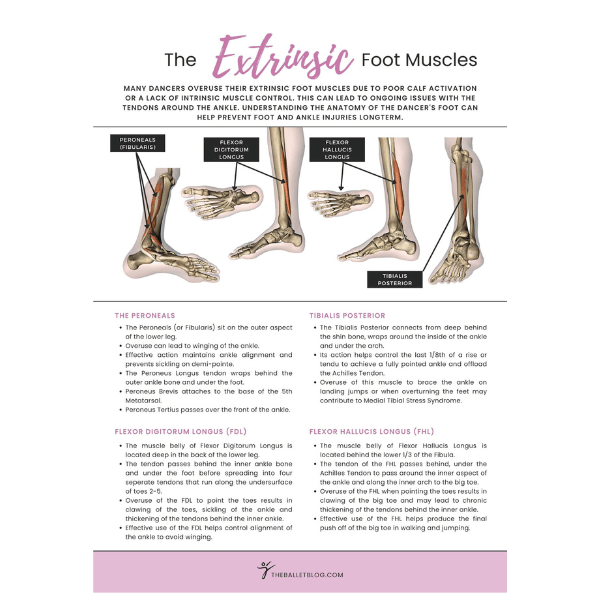

Dancing en pointe is a magnificent art form that has completely defined ballet as a practice. It poses many physical challenges for aspiring dancers with many aspects of the body's function being utilised. Over the years, we have been constantly refining our knowledge of pointe work from a physiotherapist's perspective to give you the most up-to-date ideas from the world of dance medicine. We aim to answer your questions and to help you fast-track your progression en pointe.